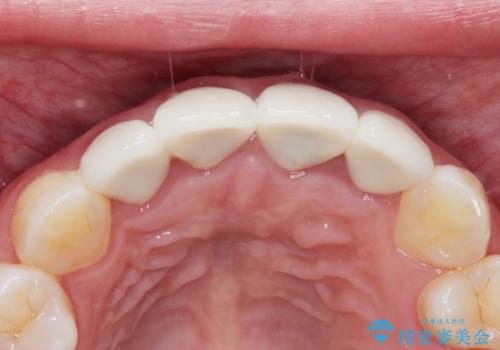

【精密根管治療+オールセラミッククラウン】より自然な前歯にしたい!

- 他院で治療した前歯が白すぎること、時々ズーンと痛むことを主訴に来院されました。

根っこの先端に病気も見つかったため、根管治療からやりかえて治療を行なっています。

被せ物の製作時は、患者さんと技工士さんが直接話をすることで、より満足度の高い治療を行うことができました。